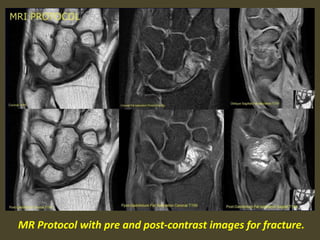

MR Protocol with pre and post-contrast images for fracture.

Scaphoid waist fracture with subtle collapse of the proximal pole, related AVN .

Diffuse enhancement of scaphoid proximal pole has good correlation

with stage group I, patchy enhancement have correlation with

grade II and III and enhancement with complete necrosis.